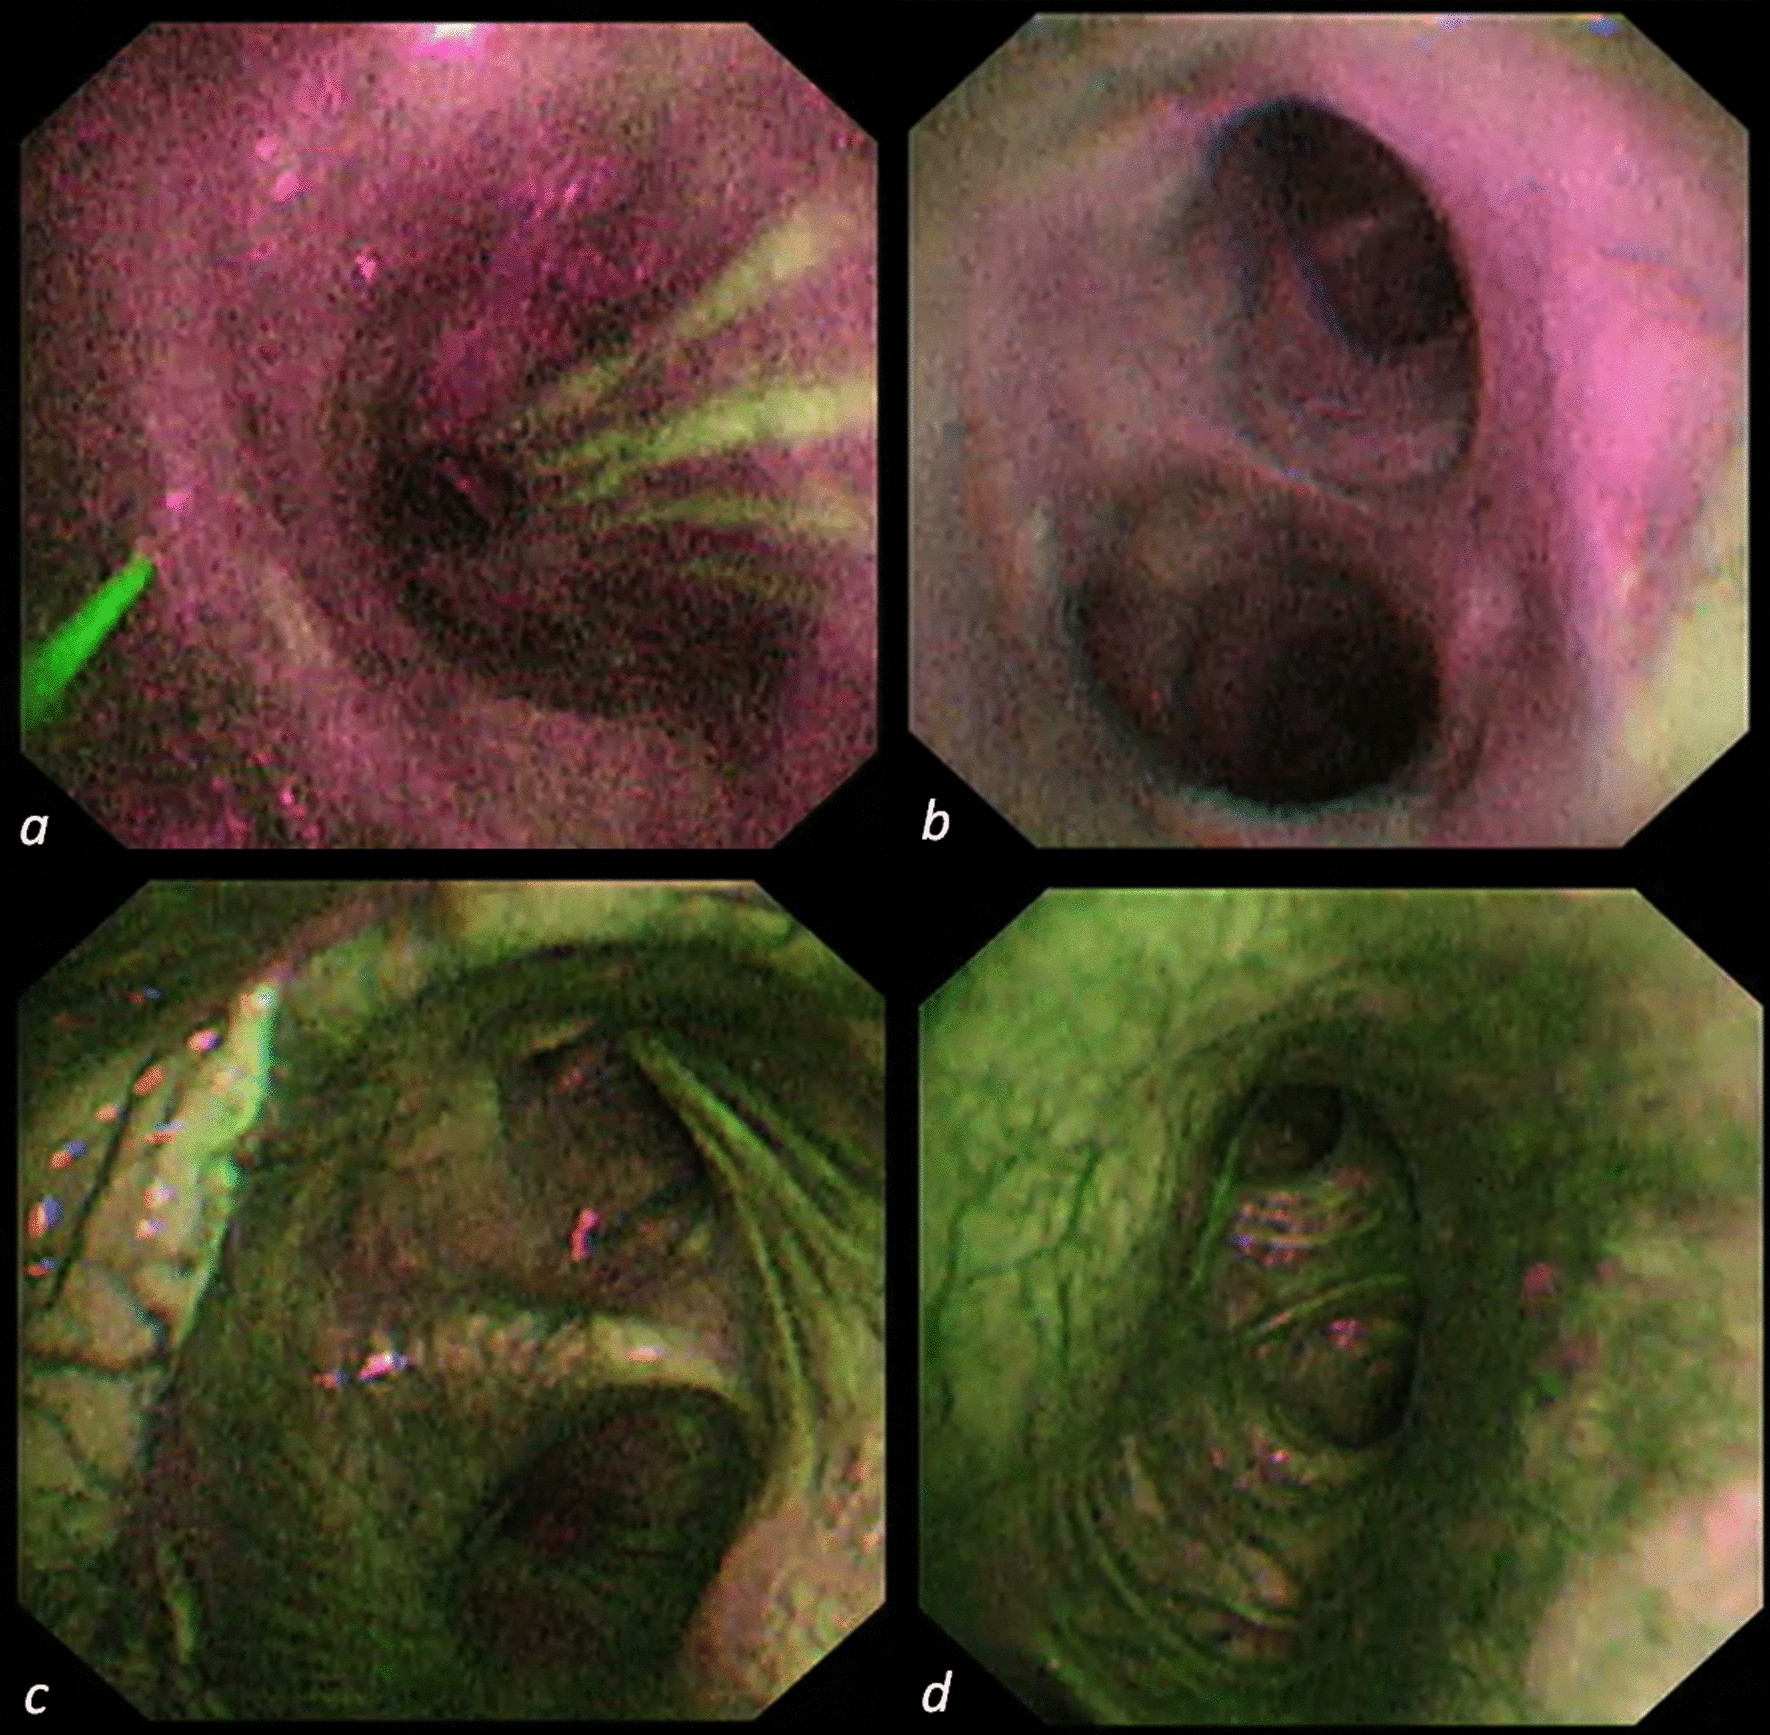

Figure 1

AFI appearance of first bronchial carina after bronchial anastomosis at baseline (a), POD28 (b), 6 months (c) and 1 year (d) after LuTx.